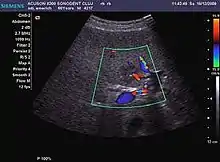

Hepatic hemangioma (2D). The lesion is located in the left hepatic lobe. Note precise delineation, their increased echogenity and the heterogeneous internal structure.

Hepatic hemangioma (CEUS). Progression of CA from the periphery toward the center of the lesion is evidenced by examination at various time intervals (a – arterial phase; b – late phase).

It is the most common liver tumor with a prevalence of 0.4 – 7.4%. It is generally asymptomatic but also can be associated with pain complaints or cytopenia and/or anemia when it is very bulky. It is unique or paucilocular. It can be associated with other types of benign liver tumors. Characteristic 2D ultrasound appearance is that of a very well defined lesion, with sizes of 2–3 cm or less, showing increased echogenity and, when located in contact with the diaphragm, a "mirror image" phenomenon can be seen. When palpating the liver with the transducer the hemangioma is compressible sending reverberations backwards. Doppler exploration reveals no circulatory signal due to very slow flow speed. CEUS investigation has real diagnosis value due to the typical behavior of progressive CA enhancement of the tumor from the periphery towards the center. The enhancement is slow, during several minutes, depending on the size of hemangioma and on the presence (or absence) of internal thrombosis. During late (sinusoidal) phase, if totally "filled" with CA, hemangioma appears isoechoic to the liver. Deviations from the above described behavior can occur in arterialized hemangiomas or those containing arterio-venous shunts. In these cases, differentiation from a malignant tumor is difficult and requires other imaging procedures, follow up and measurements of the tumor at short time intervals.[4]